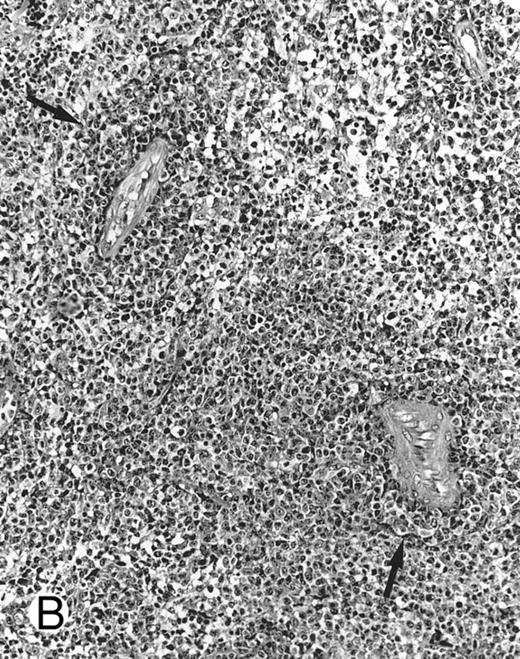

Laryngeal nasal-type NK/T-cell lymphoma relapsing as perforation of the terminal ileum (case no. 33). (A) The small bowel mucosa shows extensive necrosis and ulceration in the right field. There is also transmural lymphomatous infiltration. Note the vascular occlusion by lymphoma (arrow). (B) Higher magnification shows large and medium-sized lymphoma cells with irregular nuclear contours. The chromatin is fairly dense.

Histologically, the lymphomatous infiltrate was diffuse or patchy, with angiocentric and angiodestructive growth being observed in 30 cases (88.2%) (Figs 1 and 2). The cytologic composition was variable from case to case, including predominance of small cells, medium-sized cells, or large cells, or a mixture of these cell types (Fig 2 and 3). The tumor cell nuclei frequently showed irregular foldings and granular chromatin (Fig 2B). The larger cells possessed distinct nucleoli. The cytoplasm was moderate in amount and often pale. Karyorrhexis was usually prominent. Zonal tumor cell death, focal or confluent, was evident in 27 cases. In the 14 cases for which Giemsa-stained touch preparations were available, azurophilic granules could be identified in at least some of the neoplastic cells.